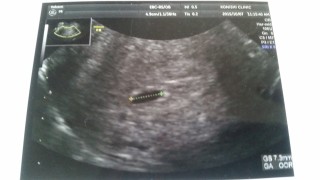

持病があり薬を飲んでるので心配でしたが、赤ちゃんの袋確認出来ました! 18㎜と言われました。次回から大学病院に移動予定です?

子宮にポリープも水もなく、胎のうも順調と言われました。意外と小さかったのですが先生は問題ないとのこと。早く胎児がみたいです。